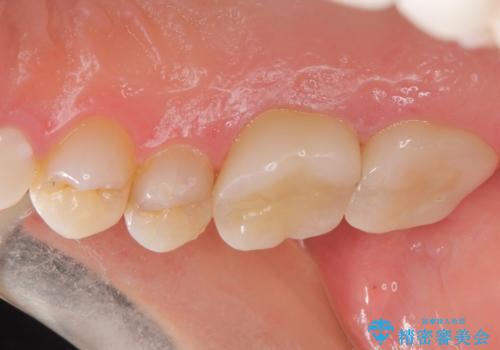

根っこの感染 再治療をしてかぶせ物を製作する

根管治療を丁寧に仕上げることで、長く安心してかぶせ物を使っていただくことができます。

かぶせものの種類:Bellezza